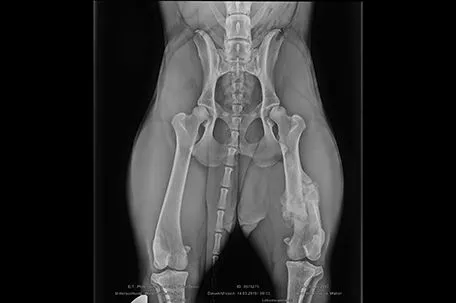

Update: Ausgesetzte Hündin in Braunau hat unbehandelte Fraktur

Röntgen zeigt einige Wochen alten Bruch des linken Oberschenkels

Auf dem Röntgenbild sieht man eine bereits mehrere Wochen alte, unbehandelte Fraktur des linken Oberschenkels.

Pfotenhilfe-Geschäftsführerin Johanna Stadler: "Ein gebrochener Oberschenkel ohne sonstige Verletzungen deutet nicht etwa auf einen Autounfall sondern viel eher auf eine rohe Misshandlung hin - neben dem Aussetzen ein weiteres strafrechtliches Tierquälerei-Delikt. Dass der Bruch dann auch noch unbehandelt blieb und zumindest über Wochen schwere Schmerzen verursacht haben muss, zeugt von besonderer Rohheit des Täters."